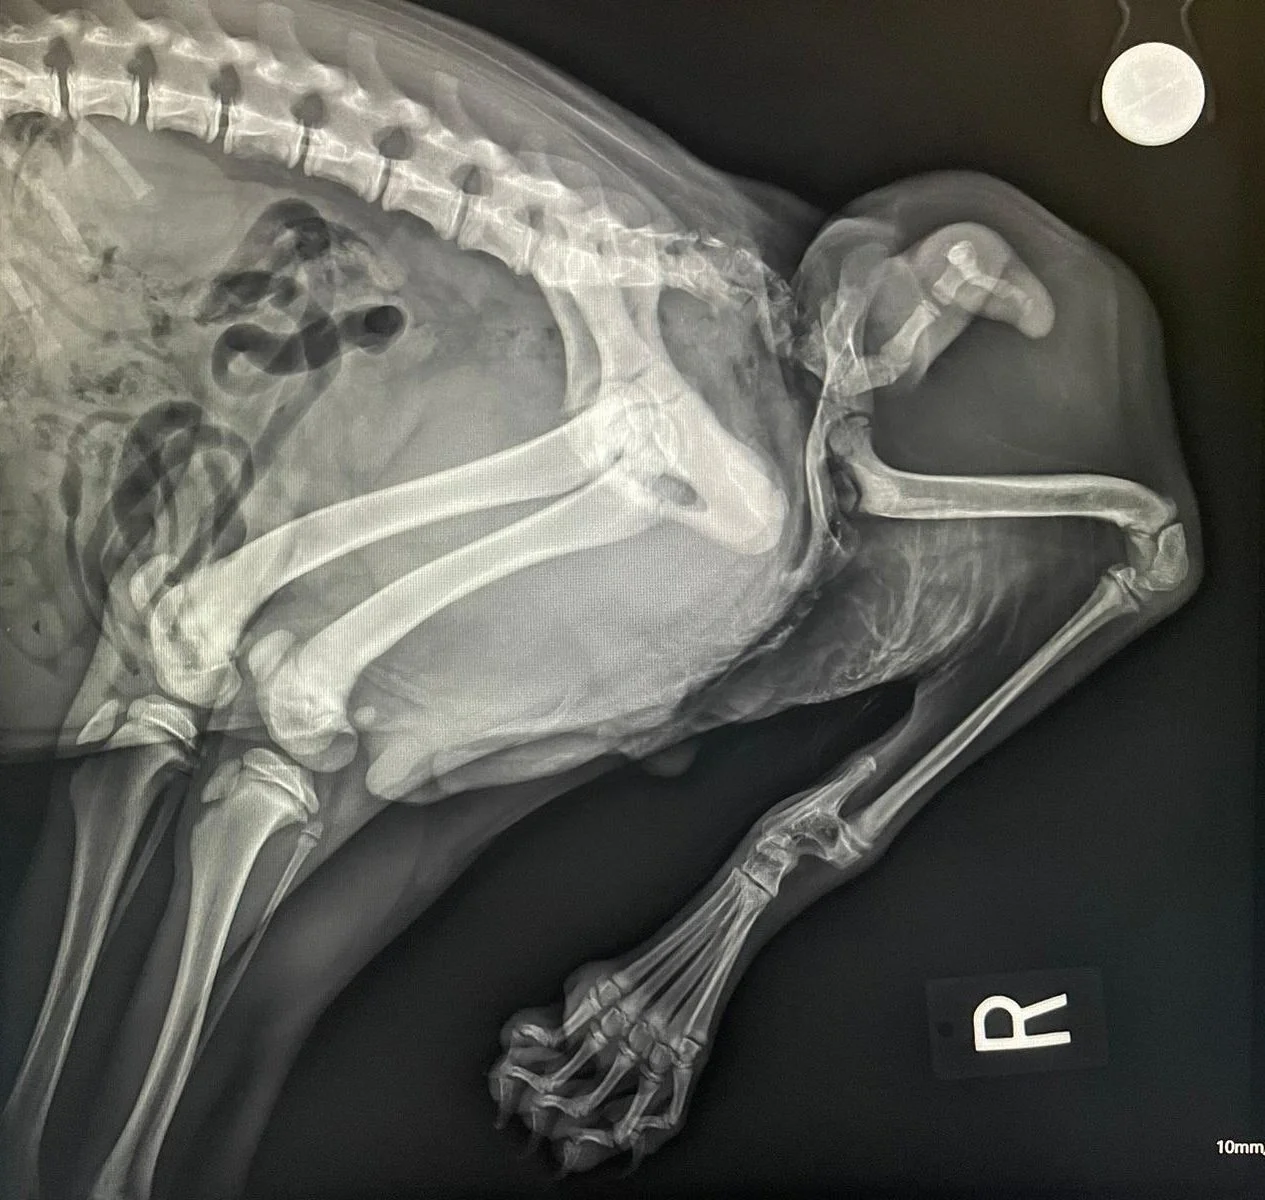

Teleradiology

Having one group overseeing all imaging modalities used in your hospital ensures seamless communication, consistent interpretation, and coordinated patient management. This ultimately enhances diagnostic accuracy and improves patient outcomes, and continuity of care reduces the risk of errors across different imaging techniques.